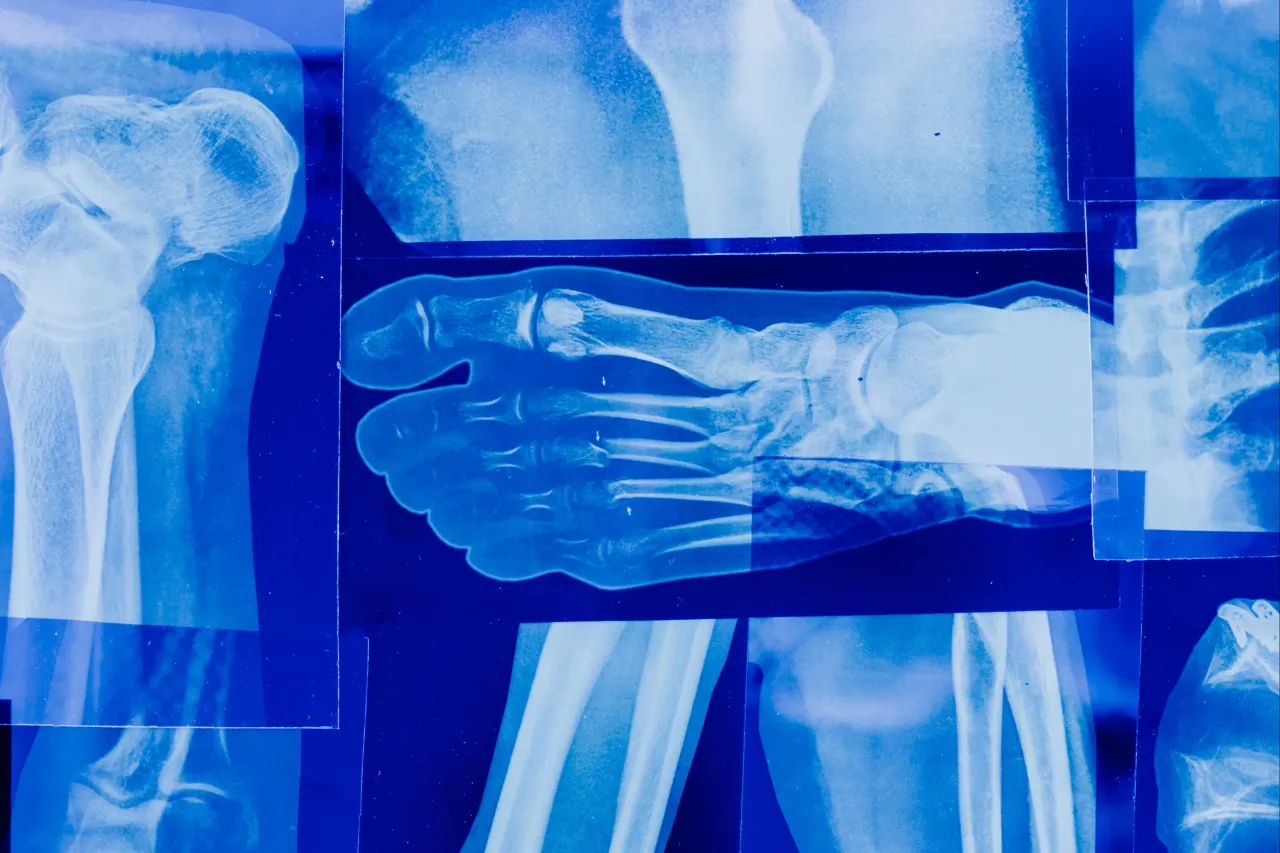

- Diagnostyka obejmuje wywiad, badanie fizykalne oraz badania obrazowe (RTG, USG, TK, MRI).

Aby postawić precyzyjną diagnozę, ortopeda często potrzebuje wsparcia w postaci badań obrazowych. Są one nieocenione w ocenie stanu kości i tkanek miękkich. Oto najczęściej zlecane metody diagnostyczne:

- RTG (rentgen): To podstawowe badanie, które pozwala ocenić strukturę kości, wykryć złamania, zmiany zwyrodnieniowe czy nieprawidłowości w ustawieniu stawów.

- USG (ultrasonografia): Idealne do oceny tkanek miękkich mięśni, ścięgien, więzadeł, torebek stawowych oraz obecności płynu w stawie. Jest bezpieczne i nieinwazyjne.

- Tomografia komputerowa (TK): Zapewnia szczegółowy obraz kości w przekrojach, co jest szczególnie przydatne przy skomplikowanych złamaniach, ocenie zmian nowotworowych czy planowaniu operacji.

- Rezonans magnetyczny (MRI): Najdokładniejsze badanie do oceny tkanek miękkich, chrząstek, więzadeł, rdzenia kręgowego i struktur nerwowych. Niezastąpione przy diagnozowaniu uszkodzeń więzadeł krzyżowych, menisków czy przepuklin kręgosłupa.

- Artroskopia diagnostyczna: W niektórych przypadkach, gdy inne badania nie dają jednoznacznej odpowiedzi, ortopeda może zdecydować się na artroskopię. Jest to minimalnie inwazyjny zabieg, podczas którego wprowadza się do stawu miniaturową kamerę, aby bezpośrednio ocenić jego wnętrze.